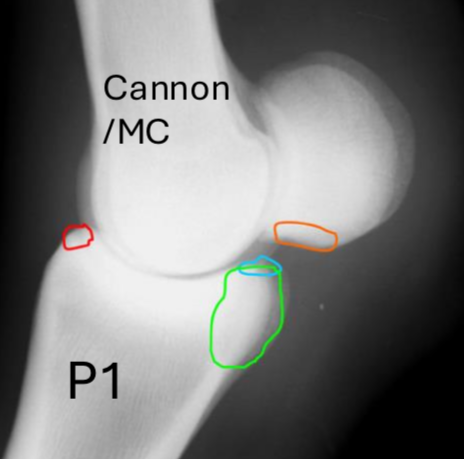

what are these fetlock fx’s

red = dorsopalmar

blue = type I prox P1 between saggital groove

green = type II wing of prox phalanx

orange = type III -basilar fx of sesamoid bones

sesamoid fx’s

red = apical

light blue = mid body split

green = basilar

dark blue = abaxial - susp lig here

pink = sagittal

Fx of MC/MT III condyle

lateral > medial